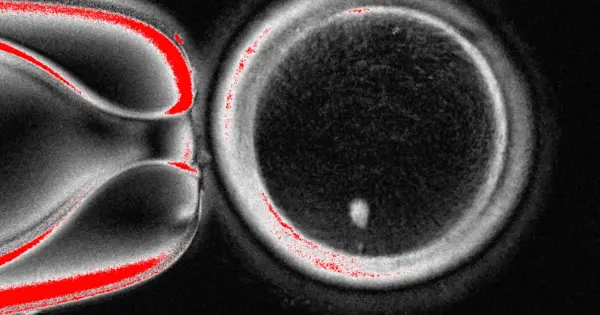

El equipo de OHSU extrajo el núcleo de una célula de óvulo humano y lo reemplazó con el núcleo de una célula de piel humana. Pero una célula de piel contiene dos conjuntos de cromosomas, y se supone que los óvulos y los espermatozoides deben contener solo un conjunto que se combine durante la fertilización. Por lo tanto, los investigadores indujeron a las células similares a óvulos a descartar cromosomas adicionales, inyectaron espermatozoides donados y activaron el desarrollo post-fertilización.

Aproximadamente el 9% duró seis días en platos de laboratorio, alcanzando la etapa de blastocisto del desarrollo temprano del embrión, antes de que se detuviera el experimento.